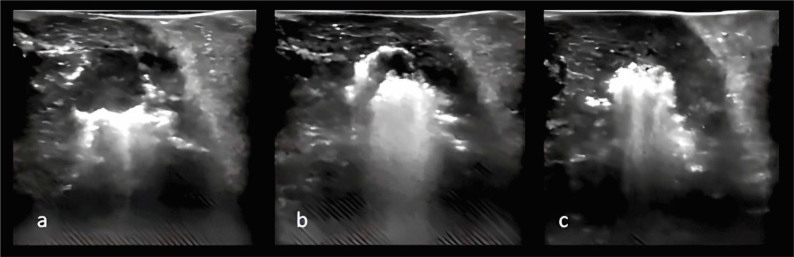

Insulinomas are rare neoplasms of the endocrine pancreas. Minimally invasive treatment options for insulinomas have gained prominence, replacing surgical resection due to its associated morbidity and mortality. Radiofrequency ablation (RFA) has emerged as a relevant treatment option. We present a case of a female patient with neuroglycopenic symptoms and severe hypoglycemic crises. The abdominal magnetic resonance imaging (MRI) showed a small nodular lesion in the pancreatic body. Laparotomy was performed, followed by RFA using a 15-mm active-tipped needle. No complications transpired, and no hypoglycemic episodes were observed during 12 months of follow-up.